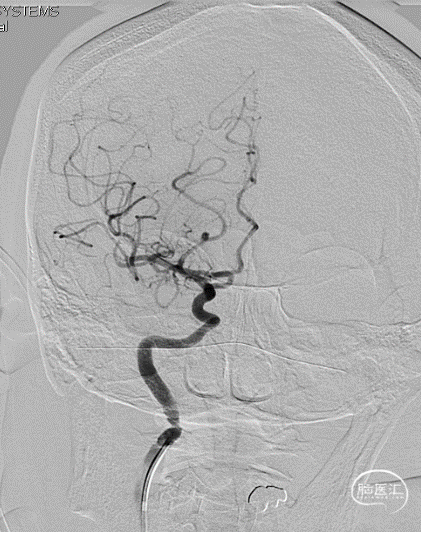

局麻,右股动脉入路置8F短鞘,导管导丝技术将8F MPA置于右C1末端,造影确认右M1急性闭塞,侧支代偿差。

以Transend导丝 + Headway21导管到达M1中段,Sofia PLUS顺畅到位(M1中段),ADATP技术抽吸取栓,一次成功取通,前向血流恢复至TICI3级,无栓子逃逸及原位狭窄,穿刺至开通时间20min(患者术中间断躁动不配合)。

以Sofia Plus进行抽吸取栓1次(ADAPT技术),实现血流复通(TICI 3级)